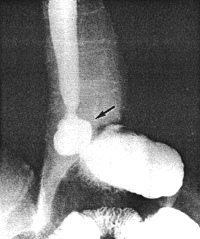

Case 32.3. F.V., male aged 75 years, was admitted for mild obstructive jaundice of 10 days' duration. There had been colicky epigastric pain for the previous 5 months, as well as acidity and heartburn for years. Oral and intravenous cholecystography revealed poor concentration of the opaque medium with calculi in the gallbladder and a dilated common bile duct containing stones. (At the time sonography of the gall bladder had not been perfected). The radiological examination showed a large, irreducible hiatus hernia (Fig. 32.3). A contraction of the pyloric sphincteric cylinder, 4.5 cm in length, with a tendency toward formation of a pseudodiverticulum on its greater curvature side, was constantly present; there was no evidence of any other lesion locally or in the remainder of the stomach. The diagnosis of contracted pyloric sphincteric cylinder, resembling AHPS, in association with hiatus hernia was made. At operation a cholecystectomy was done and calculi were removed from the common bile duct. The surgeon stated that the pyloric area of the exposed stomach felt a little thicker than usual. Had his attention not been drawn to it beforehand, it is doubtful if he would have commented on it in his operative notes. No other gastric lesion was detected. Because of the patient's age, it was decided not to repair the hernia at that time. Repeat radiographic examination 5 months later showed the irreducible hiatus hernia and the contracted pyloric sphincteric cylinder to be unchanged.

![]() |

| Fig. 32.3. Case F.V. Large irreducible hiatus hernia (black arrow). Contracted pyloric sphincteric cylinder |